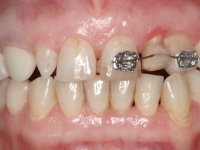

A paciente queixava-se que tinha um dente da frente a abanar, não gostava do “canino escuro” e também “queria fechar os espaços entre os dentes”. Passados 8 anos do tratamento inicial, o que motivou uma segunda fase de tratamento foi os “dois dentes da frente estarem feios”. Um ano após a última intervenção, apareceu um terceiro motivo para a terceira fase de tratamento, que foi a fratura da faceta feldspática colocada no dente 2.1.

Paciente do sexo feminino, com 47 anos não fumadora. Apresentou-se na consulta com o dente 1.3 com tratamento endodôntico e com um espigão falso coto fundido, reabilitado com uma coroa provisória. Os dois incisivos laterais superiores são conoides e de reduzida dimensão. O dente 2.2 apresenta mobilidade, consentânea com uma significativa reabsorção óssea entre o dente 2.1 e o dente 2.3 Os dois incisivos centrais estão separados por um diastema de 3mm e o dente 2.3 apresenta uma oclusão cruzada com o dente antagonista. Verifica-se também a ausência de alguns dentes posteriores e uma higiene oral razoável. Na segunda intervenção realizada passados 8 anos, verificou-se que os incisivos centrais superiores se apresentavam cromaticamente mais escuros e apresentavam um sulco longitudinal no esmalte que estando pigmentado comprometia esteticamente o sorriso. O trabalho realizado na primeira fase do tratamento mostrava-se competente estética e funcionalmente. Por fim, um ano após a última intervenção, a paciente apresentou-se com uma fratura da faceta colocada no dente 2.1 provavelmente em resultado de estar em contacto com o coto do implante. A rigidez da anquilose implantar, pode ter sido a causa desta fratura. Outros casos deste tipo de fratura já foram observados por mim em situações clínicas idênticas. A faceta do dente 1.2 apresentava-se esteticamente comprometida e a própria estrutura dentária apresentava uma pequena cárie e, pelo que se recomendaria a sua substituição.

1 ano depois, na terceira intervenção, foi proposto o seguinte tratamento:

• Confeção e colagem de uma nova faceta feldspática para substituir a fraturada. A nova faceta deverá incluir maior área dentária inter-proximal distal do dente 2.1.

• Substituir a faceta do dente 1.2 por uma coroa total em cerâmica feldspática ou por uma, agora denominada, faceta 360.

O tratamento iniciou-se com a re -preparação do coto do espigão falso coto fundido, com o objetivo de colocar as linhas de acabamento cervical com uma localização intra-sulcular e simultaneamente confecionar uma coroa provisória adaptada. Com um tratamento ortodôntico muito simples, fechou-se o diastema entre os incisivos centrais superiores e estabilizou-se esta posição com um arame colocado na superfície palatina dos centrais, funcionando como contenção. Posteriormente procurou-se fazer uma tração ortodôntica lenta do dente 2.2 com o intuito de diminuir, ainda que muito ligeiramente a perda óssea vertical nessa zona. Finalizada a tração, foi feita a extração do dente 2.2 e a zona foi reabilitada provisoriamente com uma coroa de resina composta colada aos dentes adjacentes. Foi colocado um implante dentário na zona do dente 2.2 sendo novamente colada a coroa provisória em resina, reabilitando provisoriamente a paciente durante o período de osseointegração. No dente 1.3 foi feita uma gengivectomia com bisturi elétrico, com a intenção de subir o nível cervical do 1.3 conseguindo uma maior harmonia com o dente 2.3. Estabilizados os tecidos moles, foi feita uma impressão com a técnica de moldeira aberta, utilizando silicones de adição de consistência “putty” e “light”. A recolha da cor, tanto da componente dentária como dos tecidos moles foi feita pelo ceramista no consultório.  No laboratório as impressões foram passadas a gesso e deram origem a modelos de trabalho que foram devidamente analisados. Foi decidido confecionar um “abutment” metalo-cerâmico aparafusado sobre o implante. Este “abutment” foi fundido com uma liga nobre e posteriormente revestido a cerâmica coronária e gengival. Dada a inclinação do implante o aparafusamento condicionou de forma inevitável a saída do orifício do parafuso pela superfície vestibular. No sentido de esconder esta situação, o desenho do “abutment” já foi idealizado com a intenção de acomodar na superfície vestibular a colagem de uma faceta feldspática. Este “abutment” foi provado em boca e foram feitos ajustes no componente cerâmico gengival. A sua adaptação aos tecidos moles foi feita tanto de forma subtrativa, com broca, como de forma aditiva, acrescentando resina composta de tonalidade gengival. Este acrescento de resina seria orientador do ceramista na colocação final da cerâmica de tonalidade gengival. A coroa que reabilitaria o dente 1.3 foi cimentada nesta consulta de prova com cimento de ionómero de vidro reforçado com resina composta. Finalizado o trabalho em laboratório da faceta sobre o 1.2 e o “abutment” e a faceta para o implante este foi colado em boca, após a colocação do isolamento absoluto. O trabalho satisfez plenamente a paciente. Durante oito anos a paciente foi seguida regularmente, mostrando-se agradada com o tratamento efetuado, no entanto começou a mostrar interesse em intervir esteticamente nos incisivos centrais superiores. Decidida a segunda fase da nossa intervenção, foi feita a preparação dentária dos dentes 1.1 e 2.1 para a colocação de duas facetas feldspáticas. Particular cuidado foi tido na preparação inter-proximal distal junto ao “abutment” do implante. Foi preciso avaliar muito pormenorizadamente o eixo de inserção da faceta em relação ao “abutment”. As facetas feldspáticas foram confecionadas em laboratório e posteriormente coladas em boca após a colocação de isolamento absoluto. Um ano após, iniciamos a nossa terceira fase de tratamento, após a faceta colada no dente 2.1 ter fraturado. A preparação dentária foi feita sobre a faceta colada, procurando estender mais para palatino o interface inter-proximal distal. O objetivo seria passar para mais palatino do ponto de contacto o interface faceta-dente. O preparo dentário do dente 1.2 também foi muito reduzido, limitando-se a criar um eixo de inserção. Após confecionadas a coroa total e a faceta em laboratório foram coladas em boca. Primeiro foi colada a coroa utilizando-se um isolamento relativo com teflon, posteriormente foi colada a faceta após a colocação do isolamento absoluto. Na coroa utilizei este tipo de isolamento para evitar a utilização de grampos. Seria difícil de aplicar pela forma e dimensão do dente e agressivo para os tecidos moles. Após a colagem foi avaliada a integração oclusal do trabalho.